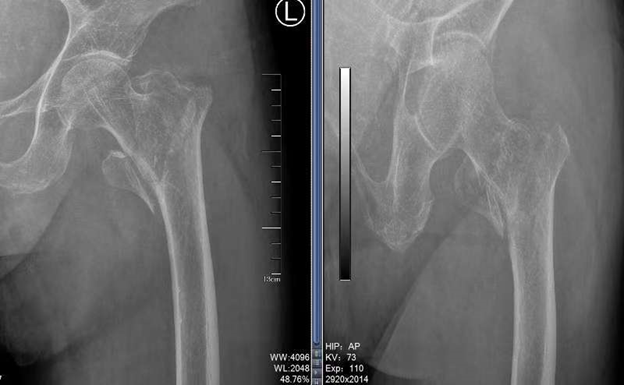

患者庄老太太,已是96岁高龄,平素体检,生活完全能够自理。此次在家中不慎摔倒,家属带着老人家至我院急诊。入院时庄老太太左髋部肿痛畸形、活动受限。影像学检查发现是“左股骨粗隆间骨折”。股骨粗隆间骨折是老年人群体常见的骨折,对老年患者危害极大,如不能得到及时正确的治疗,足以危及患者命。在1年内的死亡率可以达到20%!所以这一部位的骨折被认为是“人生最后一次骨折”。这对于已经96岁高龄的庄老太太更是一道难以迈过的坎。而保守治疗则需要长期卧床,这对老年人来说,几乎不可避免的会发生褥疮、深静脉血栓、坠积性肺炎、尿路感染等并发症,并且不排除死亡风险。手术治疗是帮助患者渡过难关的有效途径,但同样具有相当大的围手术期风险。姜为民主任在与家属充分沟通后,老太太的四位女儿一致同意手术,并对手术可能的风险表示理解。

术前的全面评估与精心准备至关重要,在同相关科室全面评估了庄老太太的情况后,我科决定采取PFNA的髓内钉微创手术方案。在各个科室的合力协作下,将患者的状态调整到理想水平,在对术中及术后各种可能的情况做了充分准备后手术开始。